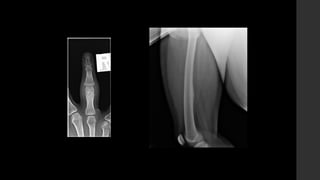

Osteoma osteoide.

• Huesos largos y

extremidades  65 – 80%.

• Falanges  20%.

• Vértebras  10%.

• RX 

 Puede ser normal.

 Reacción perióstica sólida con

engrosamiento cortical.

 El nido es, a veces, visible como una

región radiolúcida circunscrita con un punto

esclerótico central.

• TC 

 El método de elección ya que es el mejor

para caracterizar la lesión.

 Nido hipodenso rodeado de hueso

esclerótico reactivo.

 Puede verse, dentro del nido, una

calcificación central.